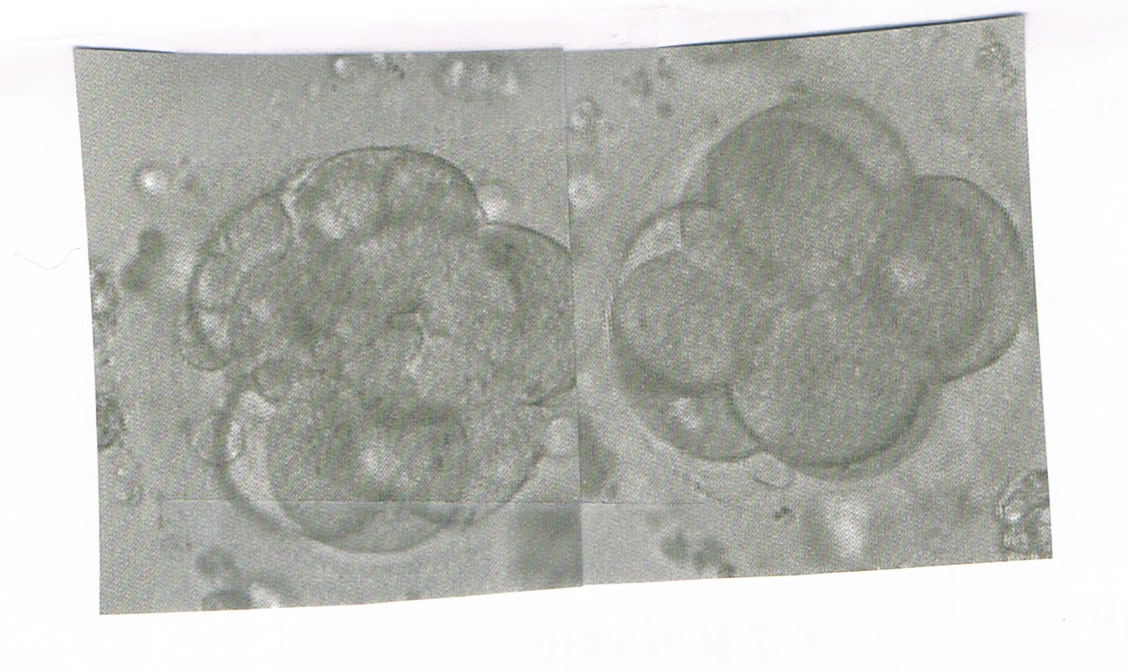

@ me: so nun habe ich 2 8-Zeller zurückgenommen nummer drei hatte bis dahin nur 5 zeller wird weiter beobachtet und soll am montag nachfragen was daraus geworden ist . die anderen beien sehen super aus ist einmal A und einmal B Qualität also dann

damit sie ein schönes Plätzchen finden und bleiben.....

schaut mal wie schön .....